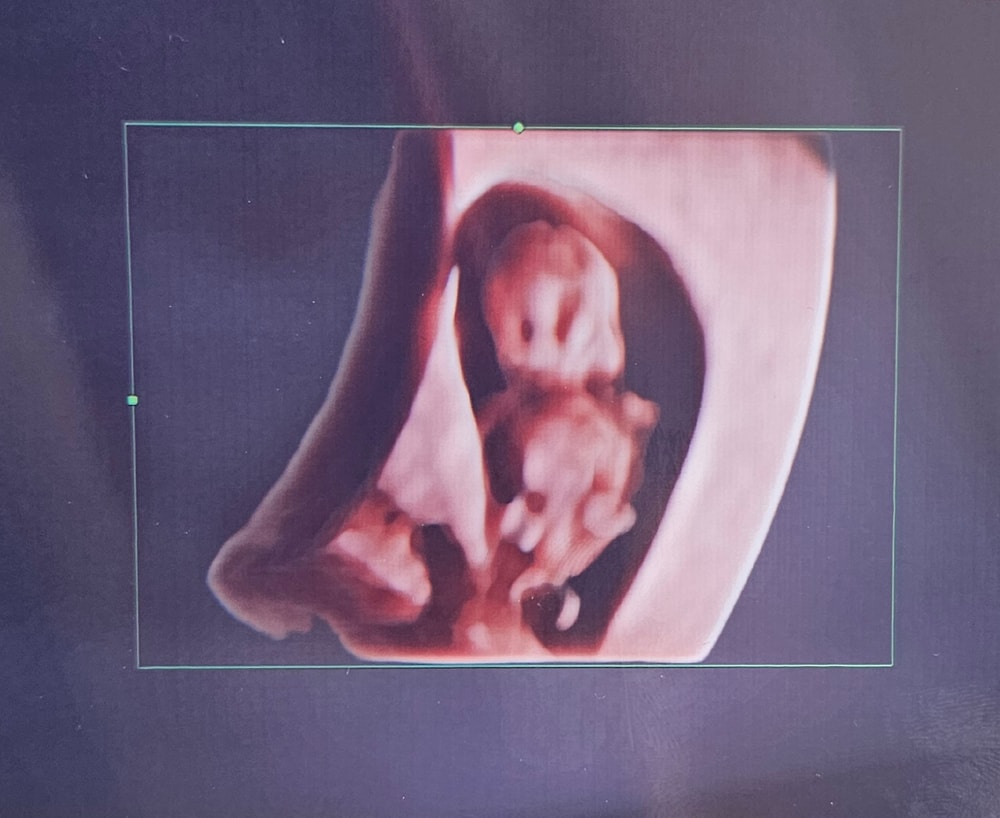

жду мальчика, 11 неделя

Узи 8н.4д. Или 40дпп

Мой пупсик уже с ножками и ручками🥰🥰🥰, растём 😇😇

Ктр 19,7

ПЯ 29,9

Чсс 184.❤️

Идём в срок! Мы очень тебя любим!!!